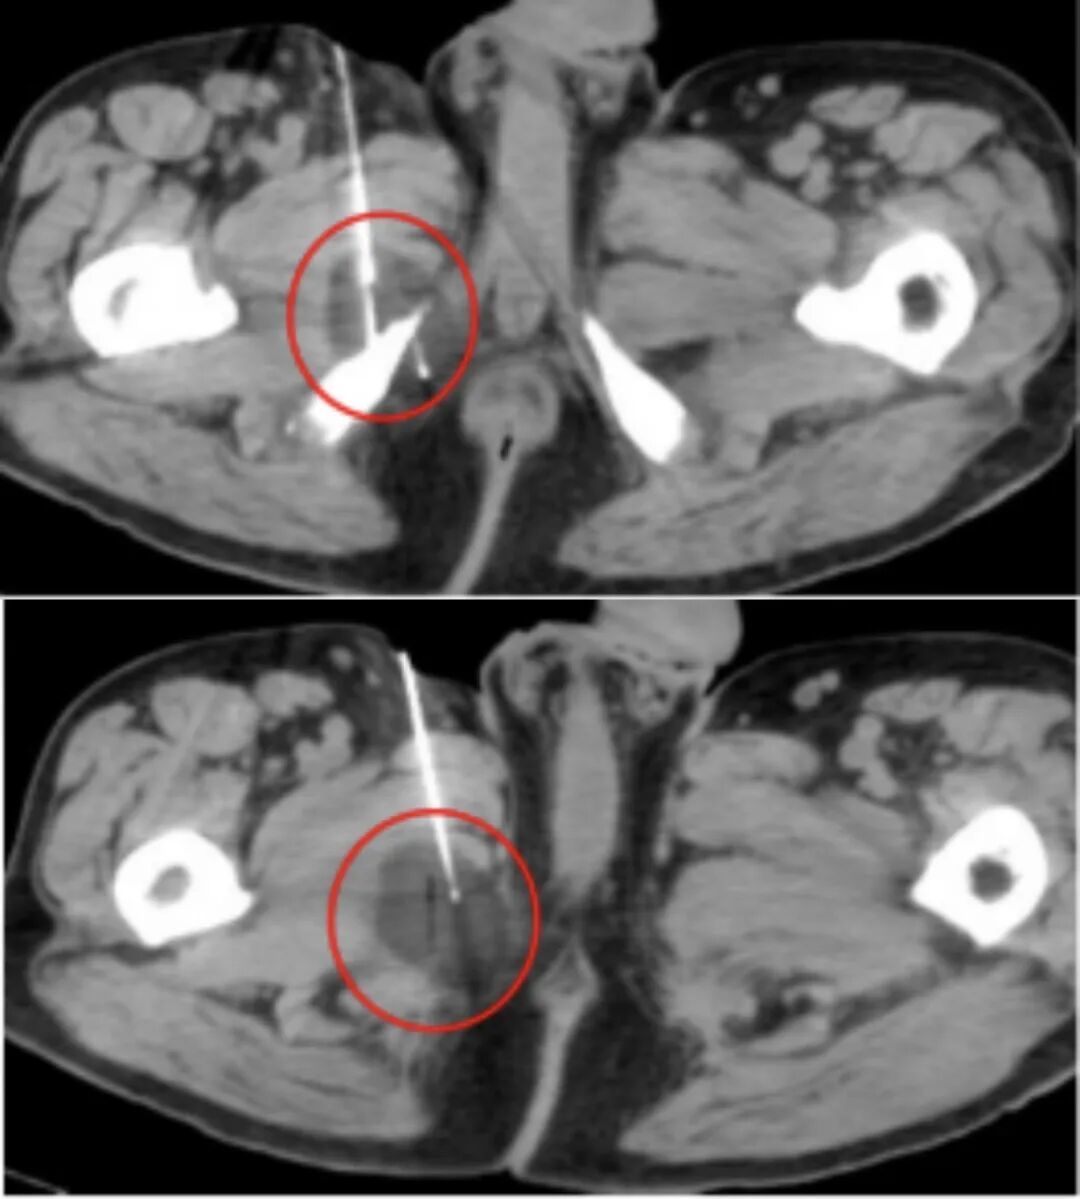

在手术实施过程中,医疗团队密切配合,在影像监测下完成相关操作。

术中情况

冷冻后,CT扫描显示冰球覆盖肿瘤,消融范围边界清晰。